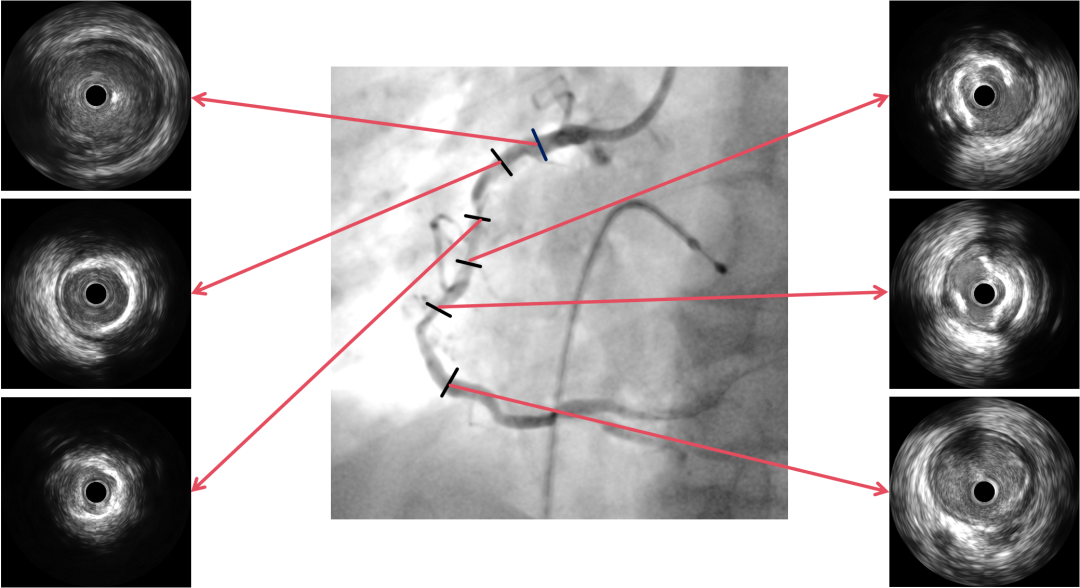

PCI过程-IVUS

IVUS可见钙化变薄、环形钙化断裂